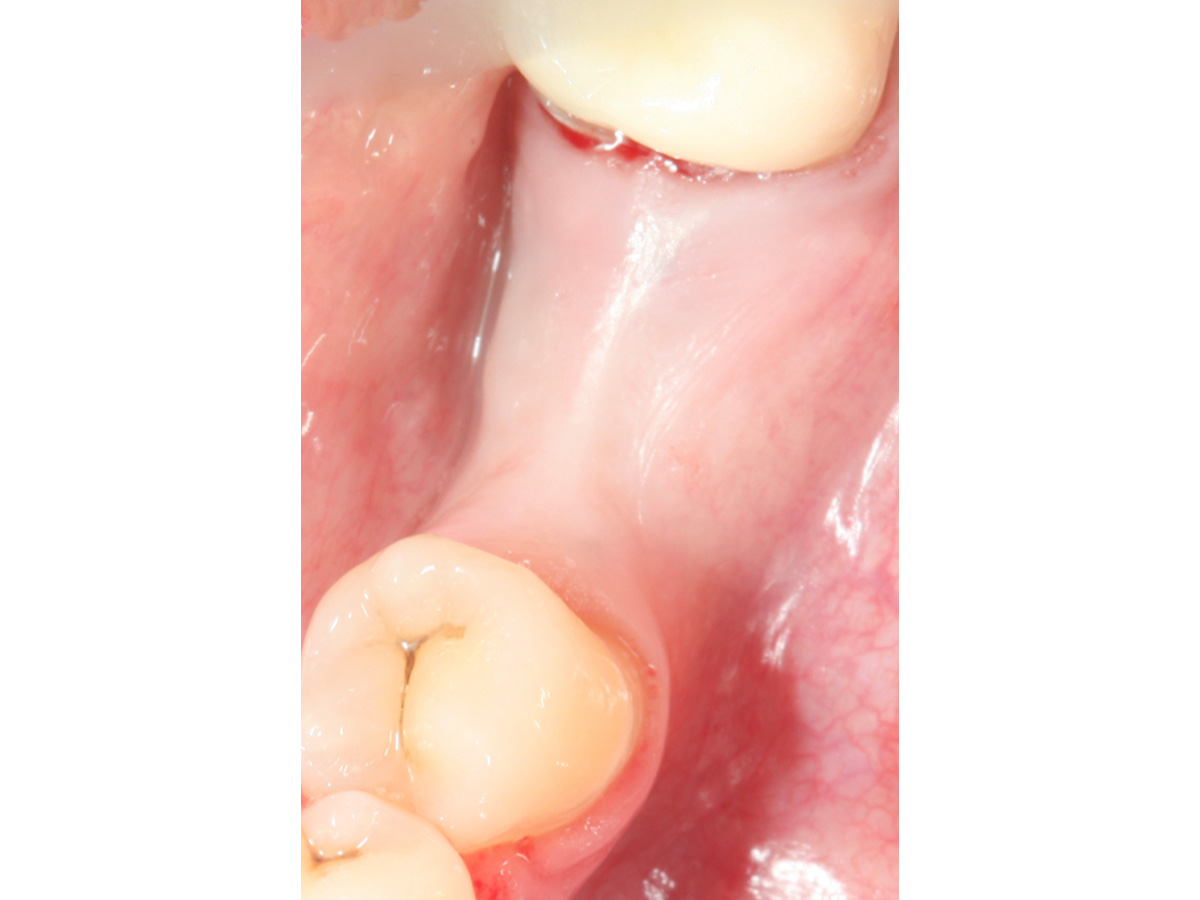

Abb. 8 zeigt die Situation vor dem Freilegen des Implantates und Abb. 9 die erfolgreiche Augmentation fünf Monate post operativ. Zu erkennen sind zwei Pins, deren Position sich im Niveau der Augmentation befinden und damit verdeutlichen, dass es zu keiner Resorption des ursprünglichen Augmentationsniveaus gekommen ist.

Abbildung 9

Augmentation nach fünf Monaten (klinisch).